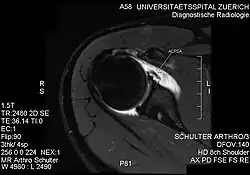

PD-weighted MRI with fat saturation of the shoulder showing an ALPSA lesion |

An ALPSA (anterior labral periosteal sleeve avulsion) lesion is an injury at the front of the shoulder associated with shoulder dislocation.[1]